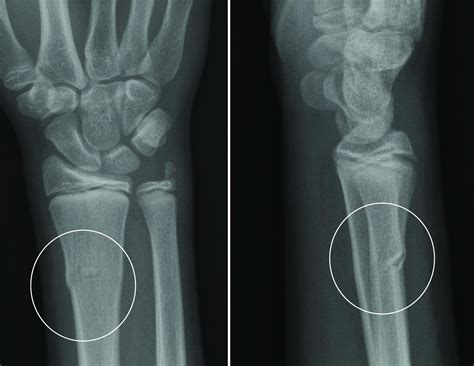

• X-rays: X-rays are the primary imaging tool used to confirm the presence and type of fracture. They provide detailed images of the bones and can help determine the severity of the injury.

Carpal Fractures Fractures in the carpals, which are the small bones of the wrist. Falls onto an outstretched hand, sports injuries, or direct impact.

Boxer's Fracture A specific type of metacarpal fracture, often involving the fourth or fifth metacarpal. Punching a hard object with a closed fist.